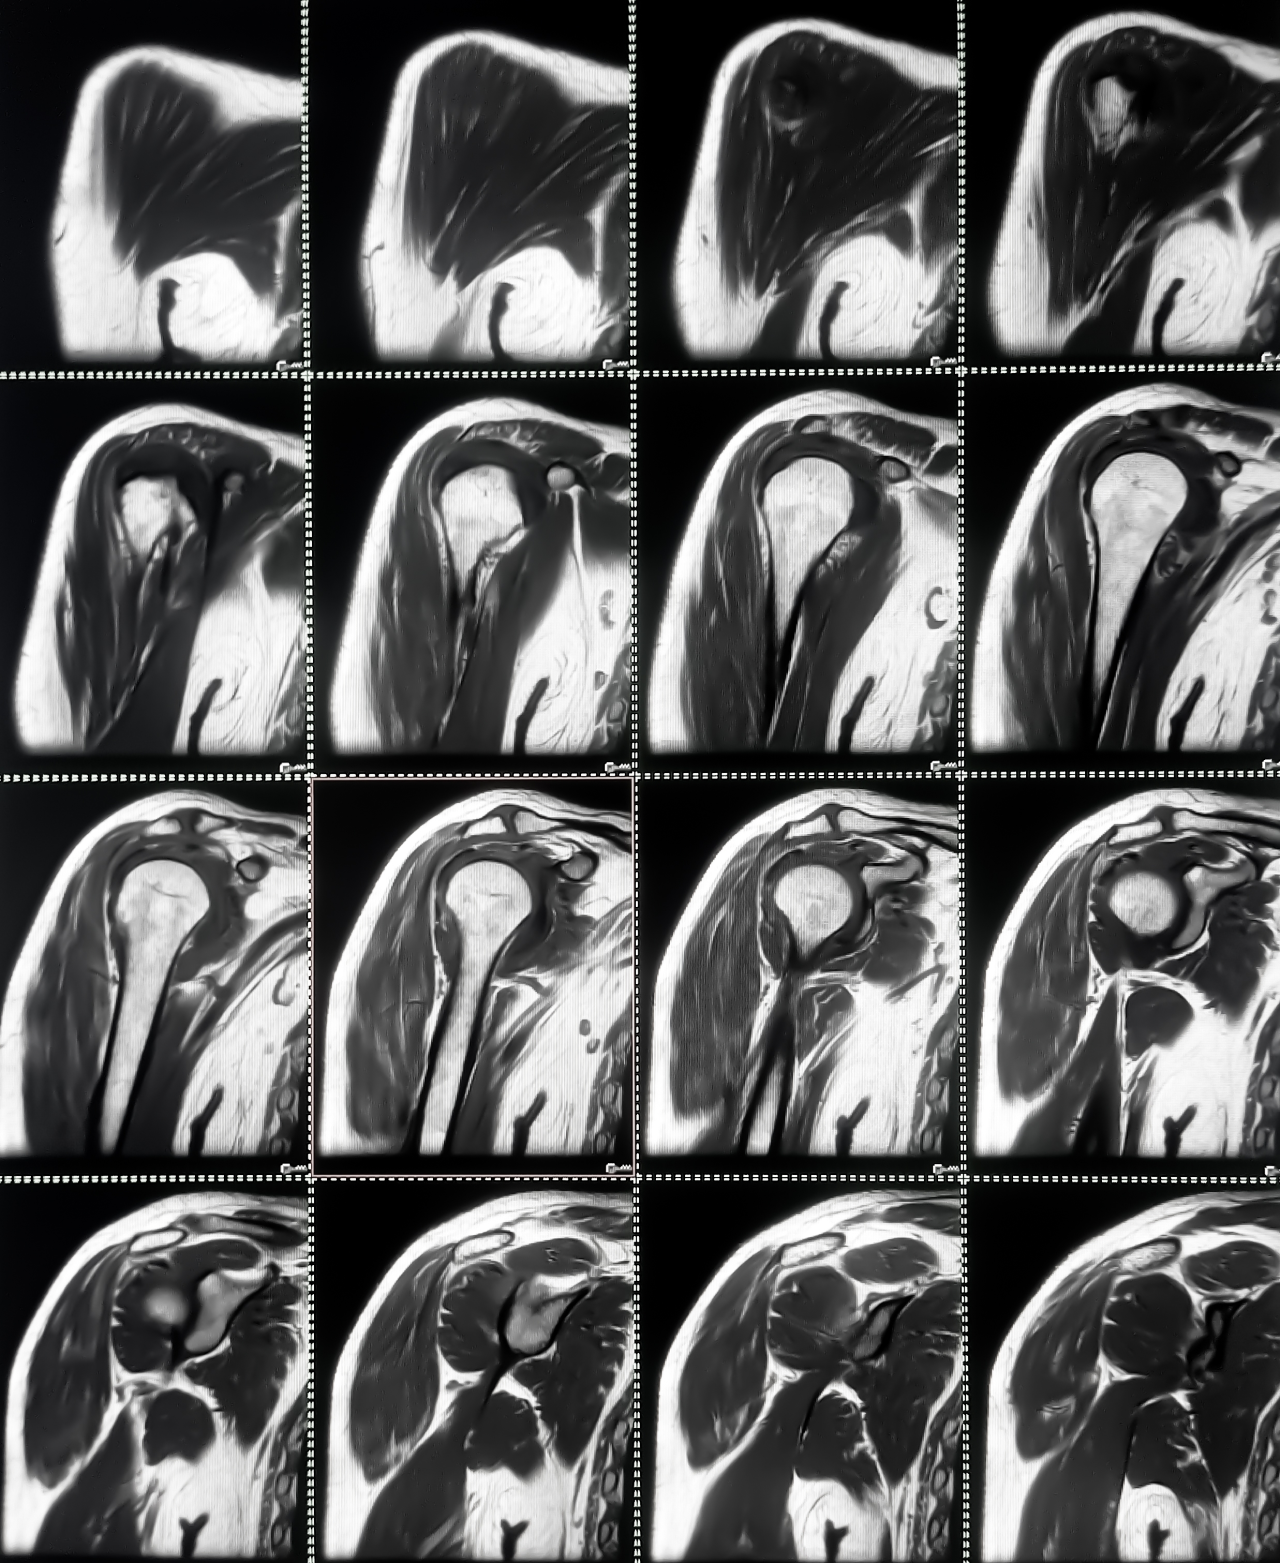

Para confirmar el diagnóstico, a la par que se valora la extensión del daño, se requerirá de estudios de imagen como la resonancia magnética. Esta prueba es la más precisa y sensible ya que permite visualizar de manera clara tanto el tendón como la ruptura.

Resonancia magnética para identificar si hay en el tendón supraespinoso rotura parcial, total u otro tipo de daño.